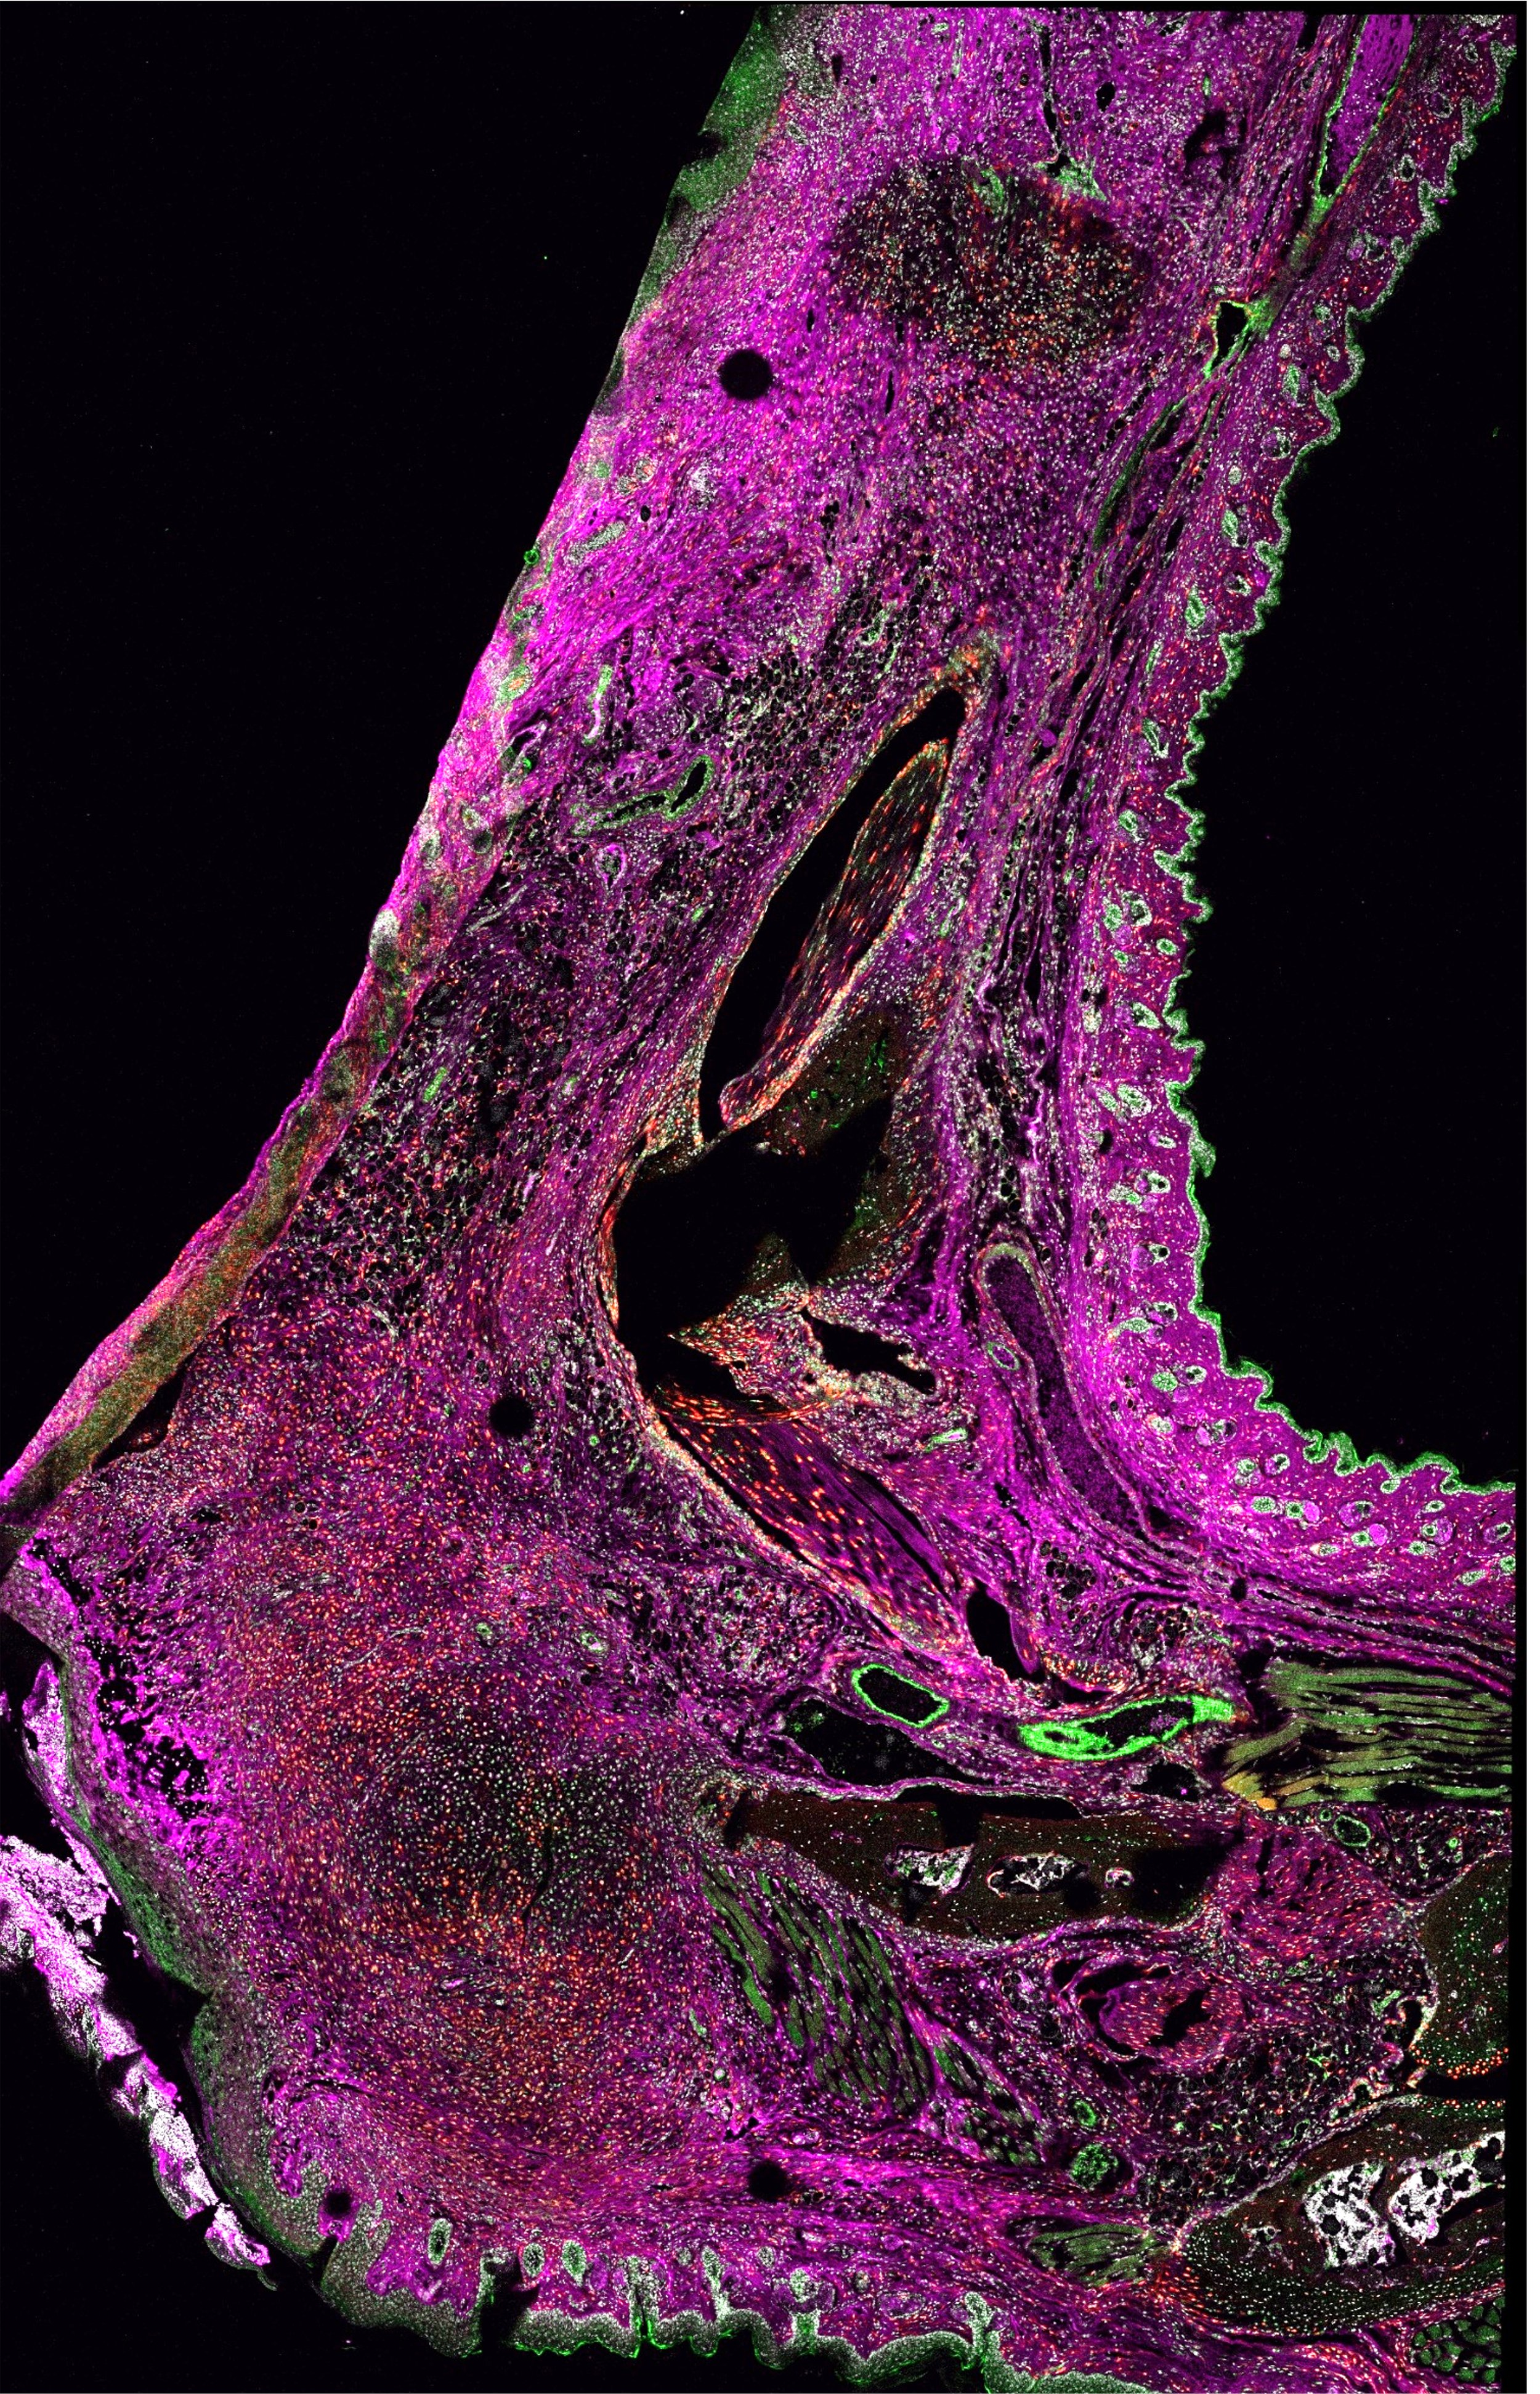

Combinations of advanced techniques such as multiphoton fluorescence and second harmonic generation imaging are used to study tissue remodeling and regeneration. Understanding these processes is critical to developing new therapies for treating blindness due to corneal scarring

Scanning confocal microscopy imaging allows for whole-section, high-resolution imaging to elucidate the spatial expression patterns of proteins of interest (purple).

The Mahendroo Lab uses the mouse as a model system to study term and preterm birth. The focus is to define the molecular steps that transition the cervix from a closed rigid structure to one that opens for a term birth.